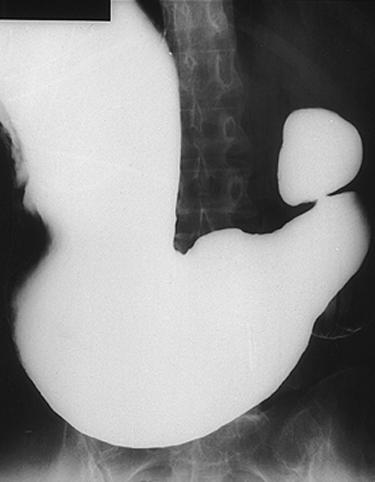

疾患(病理主体)の分類悪性上皮性腫瘍/腺癌

部位(臓器別)胃(部位)/胃角

検査方法X-P

腫瘍の肉眼分類0型(表在型)/IIc型(IIc)

病変の最大径(ミリ)25〜29

腫瘍の深達度m